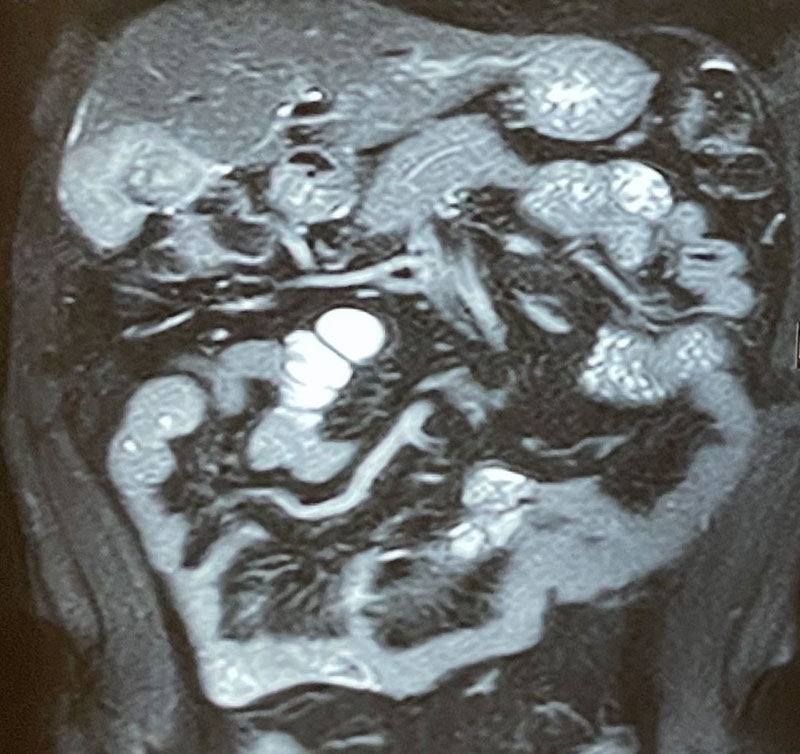

63 year old gentleman presented with right upper abdominal pain, loss of appetite, loss of weight & a USG report showing a gall bladder mass involving liver. Patient was thoroughly investigated. Investigations (PET-CT scan,MRI & tumor marker CA19-9 were highly in favour of a gall bladder cancer which could be completely removed. Hence immediate surgery was conducted without any preoperative biopsy to avoid any tumor spillage. An intraoperative controlled biopsy (Frozen section) confirmed the malignancy. The tumor was removed in toto along with portion of attached liver and draining lymph nodes. Patient recovered well in 5 days and was discharged. He was recommended postoperative chemotherapy based on the histopathology (adjuvant chemotherapy) A chemoport was inserted for the ease of delivering chemotherapy in a safe and painless manner. Patient was put on a strict follow up protocol.

1. It is vital that patient is properly investigated using PET-CT scan, MRI, Liver function tests & tumor marker CA19-9.

5. Operable and resectable patients may need (depending on the extent of disease) a radical cholecystectomy with or without liver resection / pancreatoduodenectomy / vascular resection with reconstruction and even some bowel resection.